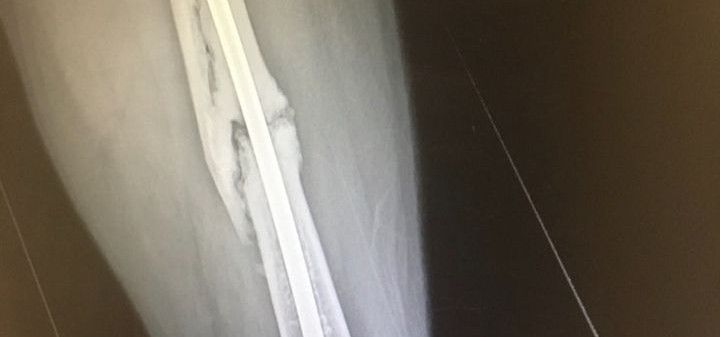

I broke the metal rod that sits in my femur. About a week ago it just folded in my leg and I have been on crutches since at home and in pain.